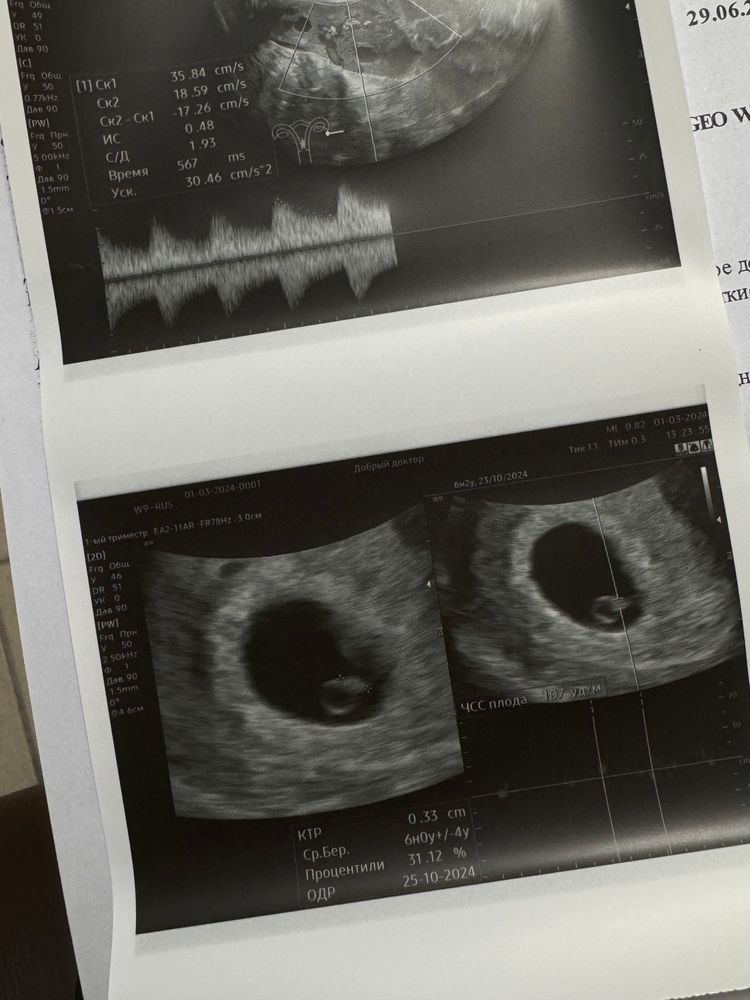

EKATERINA в Зачатие 2 года Услышала сердце🥹 6 недель. Анализы Сердечко слышно. Срок 6 недель 3 дня. Исключили пузырный занос. ХГЧ сказали растет очень быстро, и это очень хорошо. Все отлично. Слава богу. Надеюсь беременность пролетит очень быстро. Посмотрите еще 20 записей на эту тему Отменить Ответить Мари Добрый вечер! Подскажите, а чсс у вас потом разогнался? А то намерили также 107 , сказали маловато 14.09.2024 Ответить Vommar Ой слава богу!!! Поздравляю вас🙏🙏🙏🙏🩵 01.03.2024 Ответить Елена Чудесно!🥹поздравляю вас! Лёгкой беременности 🤞 01.03.2024 Ответить Lolova Все супер, все как и должно быть 🙏🏻 01.03.2024 Ответить Anna Всегда ком в горле от таких постов🥹🥹🥹 легкой беременности вам и родов в срок❤️ 01.03.2024 Ответить Силиванова Людмила 🎊🎊🎊🎉🎉🎉 01.03.2024 Ответить Попова Дарья удачи и не переживайте ✨✨✨✨✨✨✨ 01.03.2024 Ответить Моренова Рената поздравляю 🎉🎉🎉 01.03.2024 Ответить Таня Поздравляю Вас. Легкой Вам беременности 🥰❤️ 01.03.2024 Ответить Михайличенко Соня не волнуйтесь, всё будет хорошо)))))))) 01.03.2024 Ответить 8 дпп криоперенос на згт ХГЧ на 15 дпо 411,4❤🤞🤞🤞 Чаты Беременных Выберите чат: Январята-2026 Февралята-2026 Мартята-2026 Апрелята-2026 Майчата-2026 Июнята-2026 Июлята-2026 Августята-2026